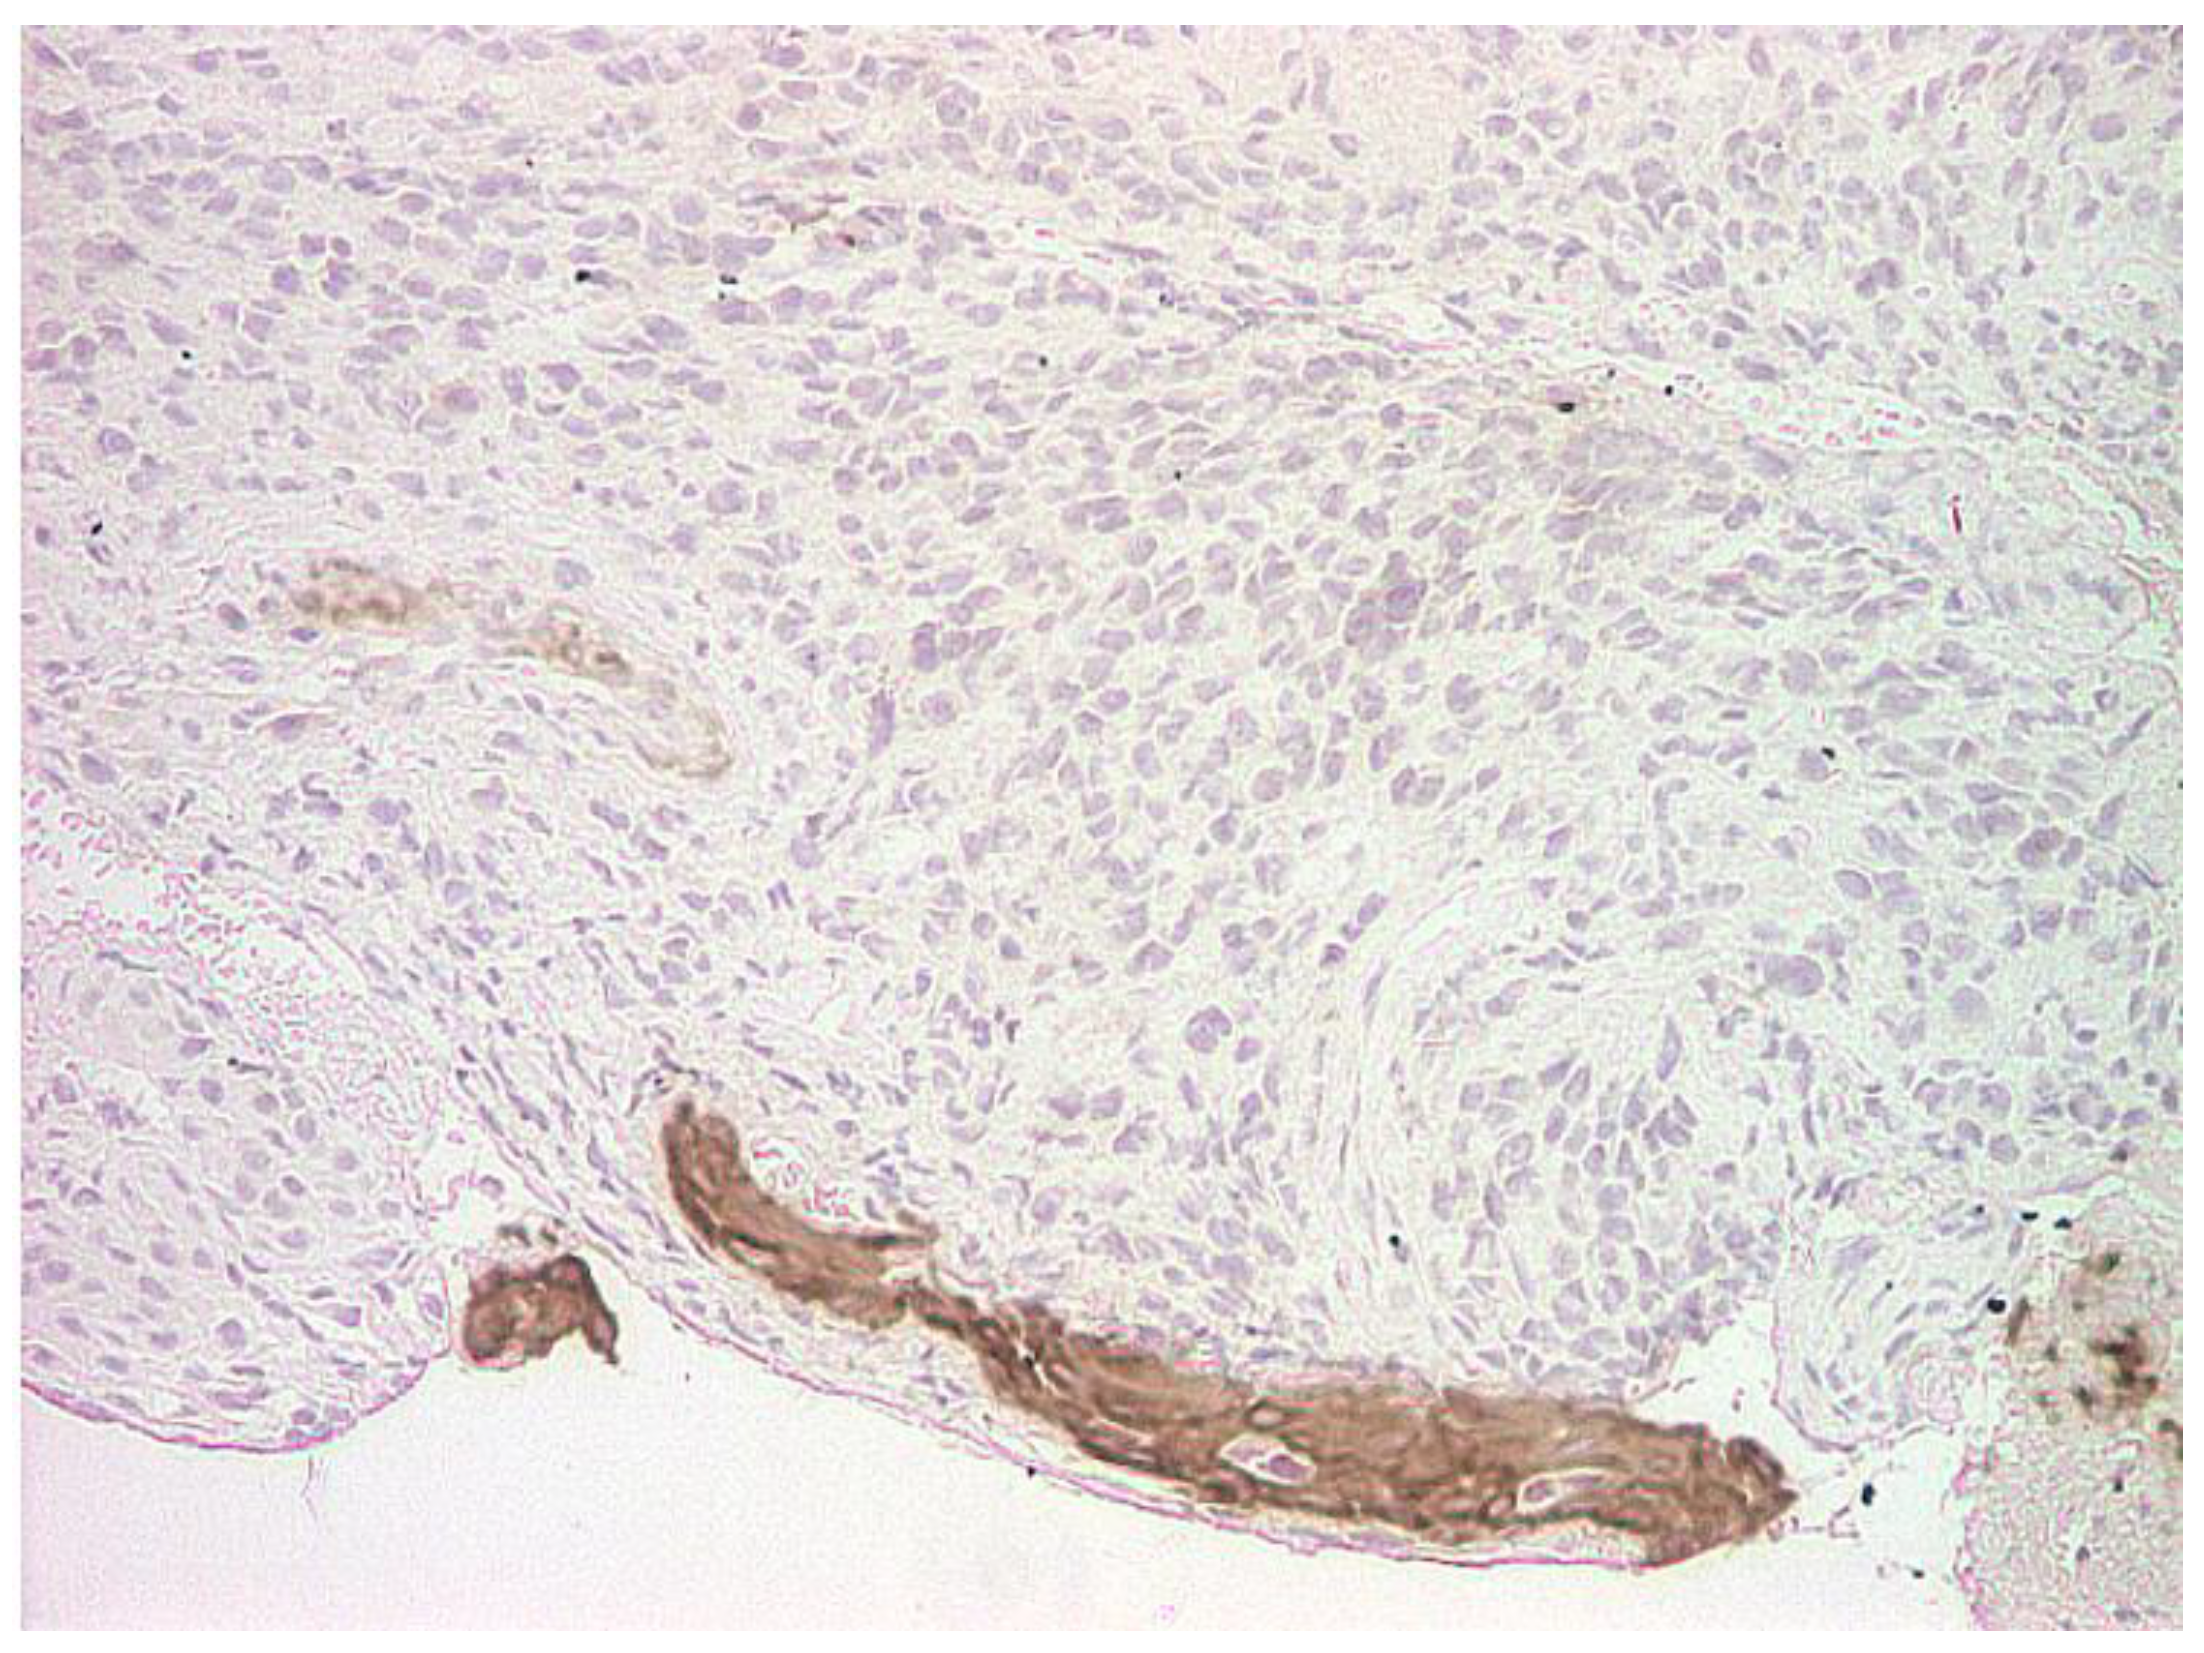

2. Case Report